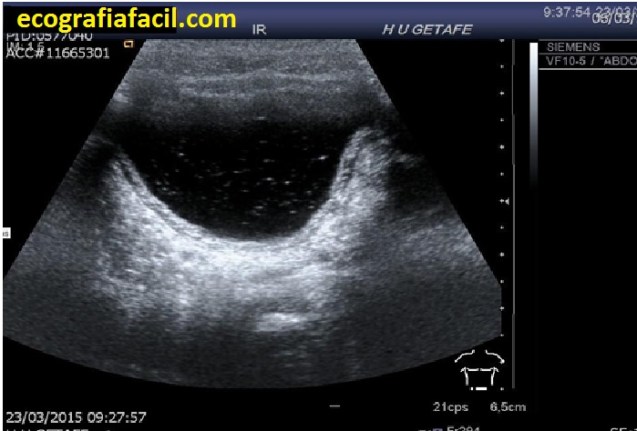

Me parece interesante que nos detengamos en un Nervio muy importante que circula por la parte posterior del muslo y que en muchas ocasiones se ve afectado e involucrado en dolor del miembro inferior, es el Nervio Ciático, que te voy a mostrar con ecografía para que lo puedas estudiar en pasos sencillos.

Es un nervio voluminoso que discurre por la profundidad del Muslo posterior, y es ecográficamente visible desde el Glúteo hasta su división cerca de la rodilla.

Ecográficamente es hiperecogénico, y se puede estudiar en todo el recorrido del Muslo.

Las neuropatías del Nervio Ciático tienen características ecográficas típicas, como aumento de grosor e hipoecogenicidad, incluso pueden presentarse lesiones tumorales de estos tejidos y se conocen como Neuroma o Tumor Neurogénico.